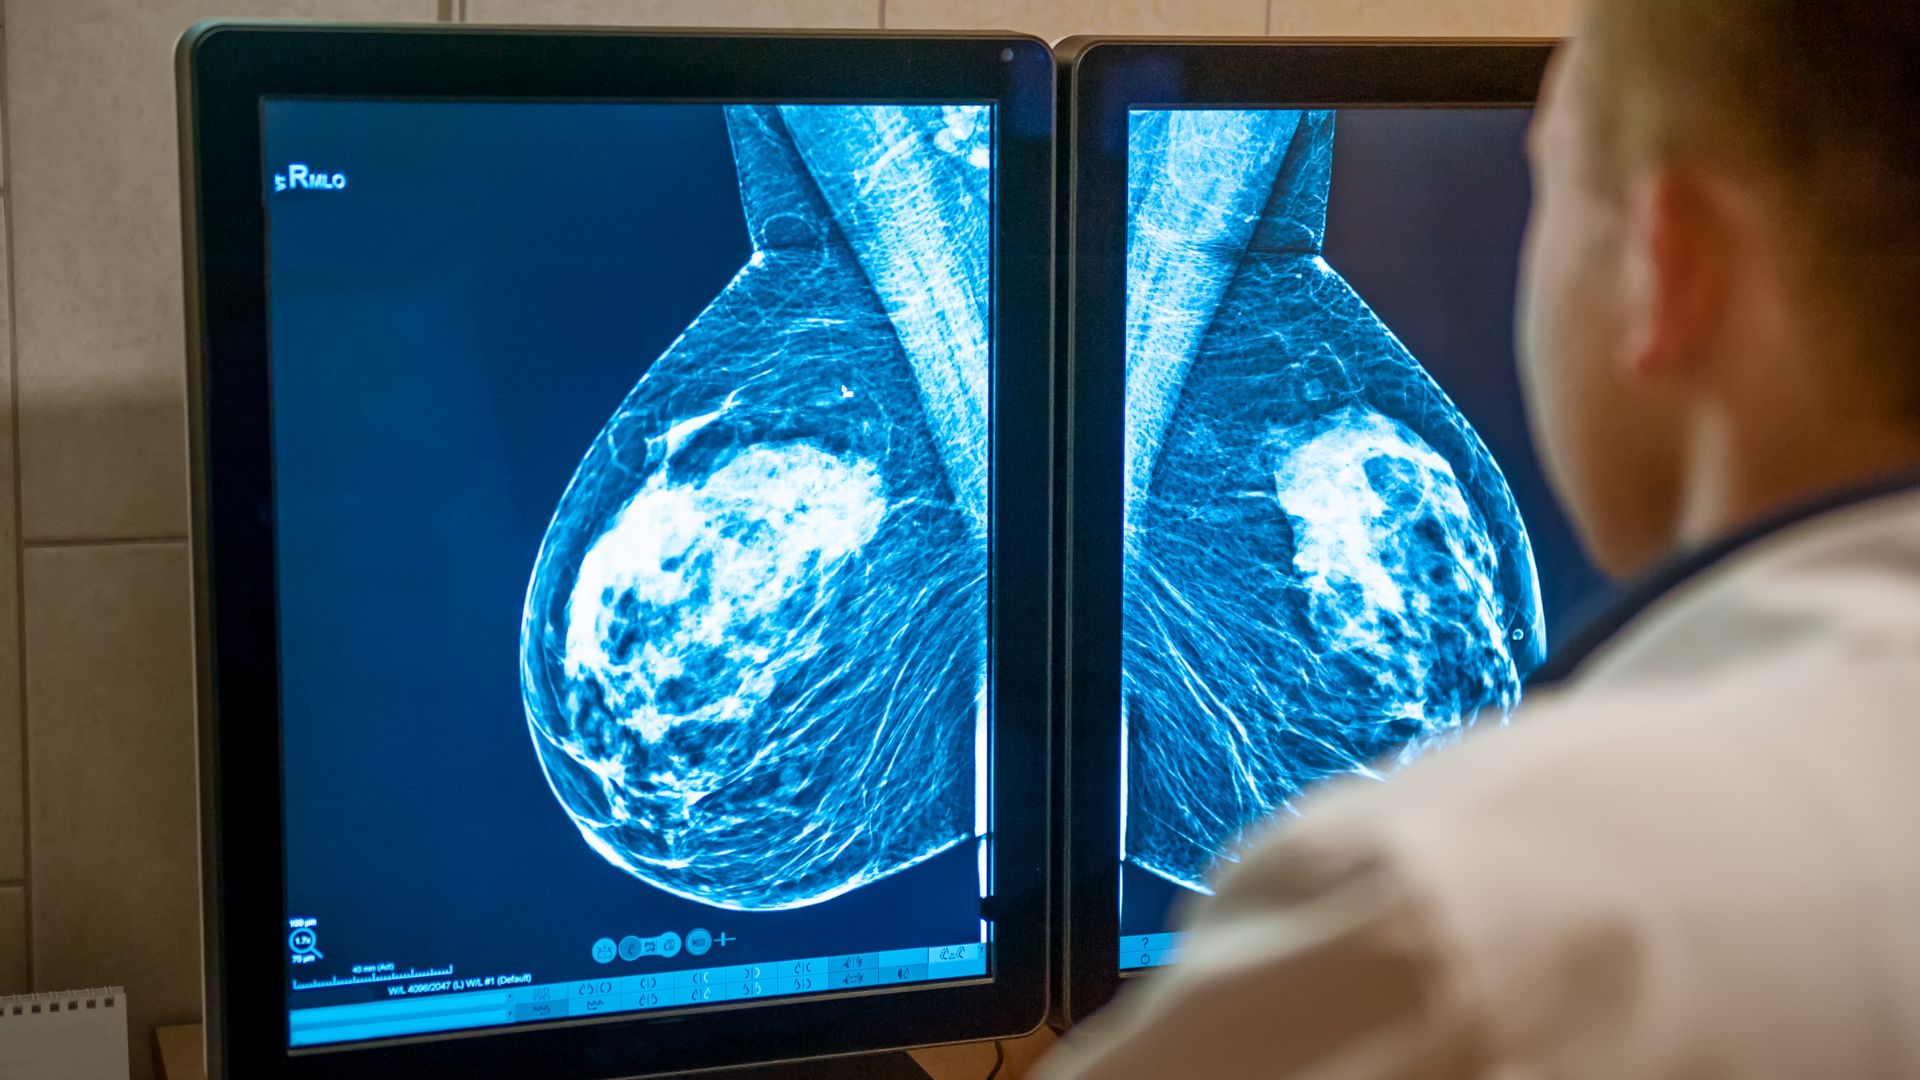

Chụp nhũ ảnh là một trong những phương pháp kiểm tra vú được sử dụng phổ biến nhằm phát hiện sớm các bất thường. Tuy nhiên, do phải tác động trực tiếp lên vùng ngực, nhiều người cảm thấy e ngại và hình dung đây là một trải nghiệm đau đớn. Việc thiếu thông tin chính xác có thể khiến không ít phụ nữ trì hoãn việc kiểm tra, làm giảm cơ hội phát hiện sớm các vấn đề sức khỏe quan trọng.

Theo chuyên gia y tế, chụp nhũ ảnh có thể gây cảm giác khó chịu hoặc đau nhẹ, nhưng mức độ thường không nghiêm trọng và chỉ kéo dài trong thời gian rất ngắn. Phần lớn người được chụp mô tả cảm giác này giống như bị ép chặt trong vài giây, sau đó nhanh chóng chấm dứt khi kết thúc thao tác.

Từ góc độ y tế, lợi ích của chụp nhũ ảnh trong việc phát hiện sớm các bất thường ở vú lớn hơn rất nhiều so với cảm giác khó chịu tạm thời trong quá trình thực hiện. Khi hiểu rõ điều này, người được chụp thường cảm thấy yên tâm và hợp tác tốt hơn, giúp quá trình diễn ra nhanh chóng và hiệu quả.